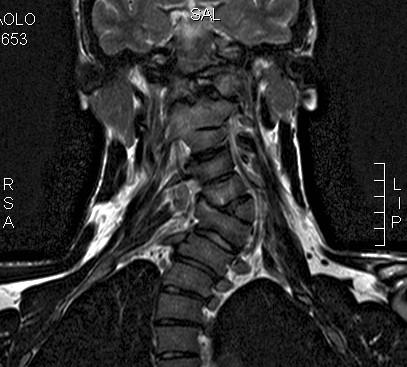

This is an image of the front of my neck taken 2 years ago. I have others but this is very good. I must say it’s a shock for me to see it, every time. I usually do the exams, take a quick look at the results and archive them with a feeling of sadness and rejection.

As you can see the presence of C6 caused a severe curve. The other cylinders found a way, a characteristic way, to adapt to the presence of the freak. Diagnosis talk about cervical scoliosis, which is quite uncharacteristic. It’s very localized. My spine is straight from the middle down, but very curvy in the trapezes area. Usually the curves related to a scoliosis due to hemivertebrae are wider, because hemivertebrae happen much more frequently in the lumbo-dorsal area.